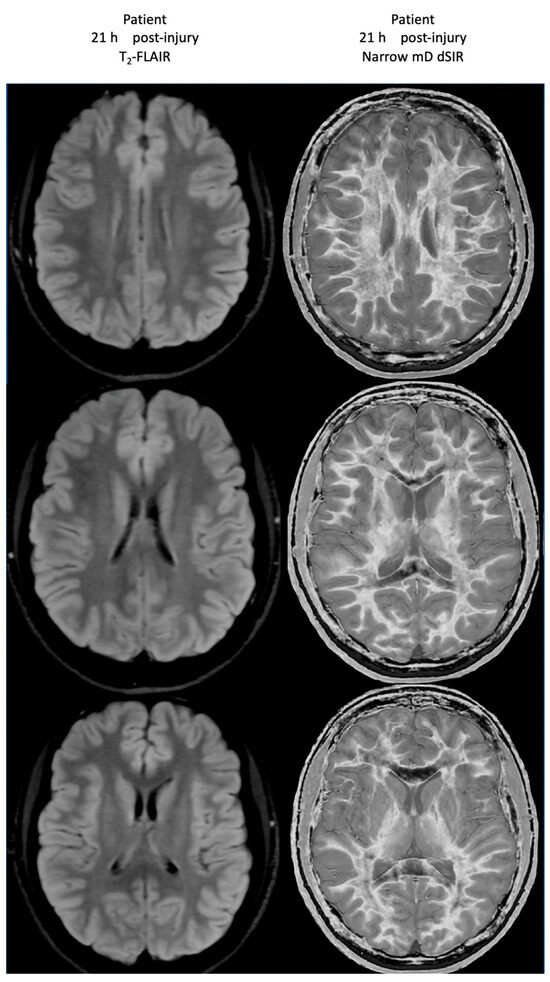

At his first examination 21 h post-injury, his T2-FLAIR images were normal (Figure 20, left column) but his narrow mD dSIR images (right column) showed extensive high signal abnormalities in the white matter of his cerebral hemispheres with sparing of the anterior and posterior corpus callosum, as well as some sparing of the peripheral white matter in the cerebral hemispheres, consistent with a whiteout sign grade 4. This is quite different from the low signal seen in the white matter of the age matched normal control dSIR image shown in Figure 16, which is whiteout sign grade 1.

Figure 20.

Case 2 Acute mTBI imaged at 21 h post-injury. T2-FLAIR (left column) and narrow mD dSIR (right column) images. No abnormality is seen on the T2-FLAIR images. On the dSIR images, extensive high signal abnormalities are seen in most of the white matter with sparing of the anterior and posterior central corpus callosum and posterior white matter of the cerebral hemispheres. The appearances are consistent with a whiteout sign grade 4.

Figure 21 shows his dSIR images at 21 h post-injury (left column) and at 64 h post-injury (right column). There is a marked difference between the dSIR images at 21 h (left column) and 64 h (right column) consistent with complete regression of his whiteout sign over 43 h (i.e., in just less than two days) from grade 4 to grade 1. Case 2’s 64 h post-injury dSIR images (right column) are similar to the normal control images shown in Figure 16.

Figure 21.

Case 2 Acute mTBI imaged 21 h and 64 h post-injury. Narrow mD dSIR images. On the images obtained at 21 h post-injury, extensive high signal abnormalities are seen in most of the white matter with sparing of the anterior and posterior central corpus callosum and peripheral white matter of the cerebral hemispheres (left column). On the images at 64 h post-injury, normal low signal white matter is seen in the hemispheres (right column). The images show marked regression of abnormalities over 43 h (i.e., just less than two days). The boundaries between white and gray matter and around the lateral ventricles become more obvious after regression of whiteout sign from grade 4 (left column) to grade 1 (right column).

No abnormality was seen on Case 2’s T2-FLAIR images either at 21 h or 64 h post-injury.